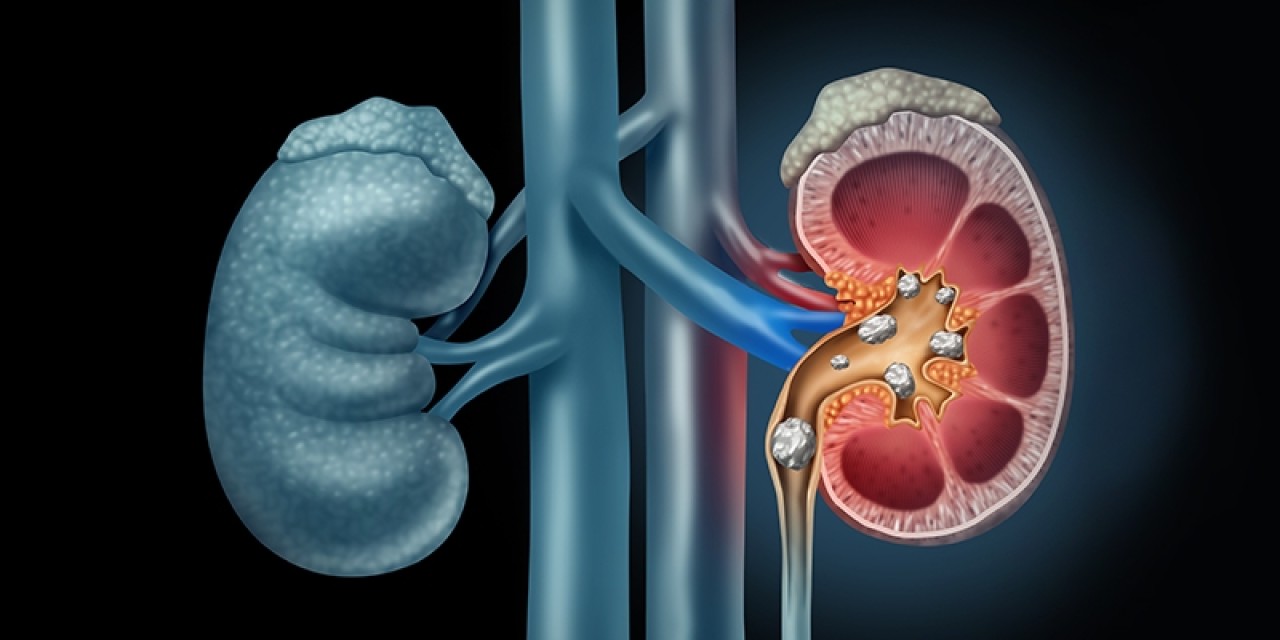

به گزارش نبض نگار: دلایل زیادی برای تشکیل سنگ کلیه وجود دارد. کمآبی بدن شایعترین عامل است. نوشیدن حداقل 8 تا 10 لیوان آب در روز، بدن را هیدراته نگه میدارد و خطر تشکیل سنگ کلیه را کاهش میدهد. رژیم غذایی و عوامل ارثی نیز با تشکیل سنگ مرتبط هستند. درد ناشی از سنگ میتواند بسیار شدید باشد و معمولاً به صورت موجهایی از 20 دقیقه تا 60 دقیقه طول میکشد.

انواع سنگ کلیه

سنگها بر اساس نوع کریستالهایی که از آنها تشکیل شدهاند نامگذاری میشوند:

سنگهای کلسیم-اگزالات و کلسیم-فسفات. سنگهای کلسیمی میتوانند زمانی تشکیل شوند که غذاهای سرشار از اگزالات یا کمکلسیم مصرف کنید و مایعات کافی ننوشید. سنگهای کلسیم-اگزالات شایعترین نوع سنگ کلیه هستند.